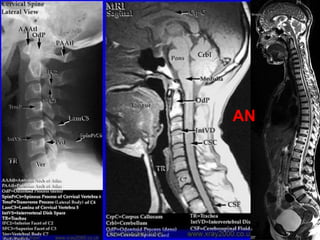

Magnetic resonance imaging

MRI

( study of choice )

AN

T1 T2

Plain X-rays,

CT

Imaging Decisions

Plain Radiographs (x-rays) are usually

the first series of images to be

ordered by the physician.

If fractures, or other bony defects,

are suspected, CT images can provide

very detailed information.

When soft tissue injury is suspected,

MRI is usually the imaging

technology of choice.

IMAGING DECISION

It is often necessary to utilize multiple imaging

modalities. X-ray, CT and MRI to get all the

information required for treatment.